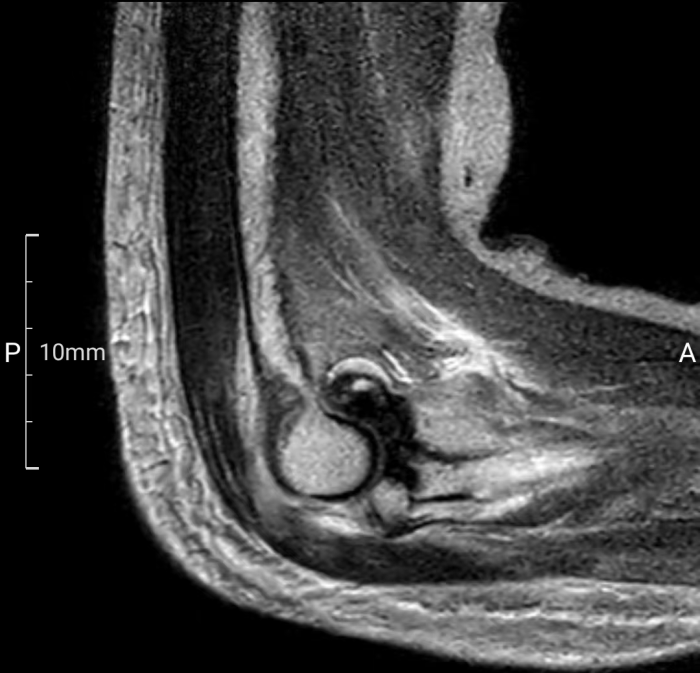

术前二维影像

患者梁女士因不慎跌倒导致右肘关节疼痛并活动受限,经X线检查确诊为肘关节恐怖三联征。面对这一复杂病情,张立主任迅速组织科室医生及3D打印中心技术人员进行病例讨论,并决定采用3D打印桡骨小头置换术进行治疗。

术前,南溪山医院3D打印中心利用高精度扫描技术获取患者肘关节的三维数据,并进行参数化分析,为患者量身定制了3D打印桡骨小头假体。这一假体不仅与患者骨骼高度匹配,还能在手术中即插即用,极大地缩短了手术时间,并确保了手术的精准性和安全性。

手术由张立主任及贵鹏医师团队共同完成。术中,医生们通过5厘米的切口暴露骨折部位,并依据术前规划精准处理骨折断端。随后,3D打印桡骨小头假体被顺利植入,实现了对桡骨头关节面的完美重建。术后,患者恢复顺利,基本功能得到有效恢复。